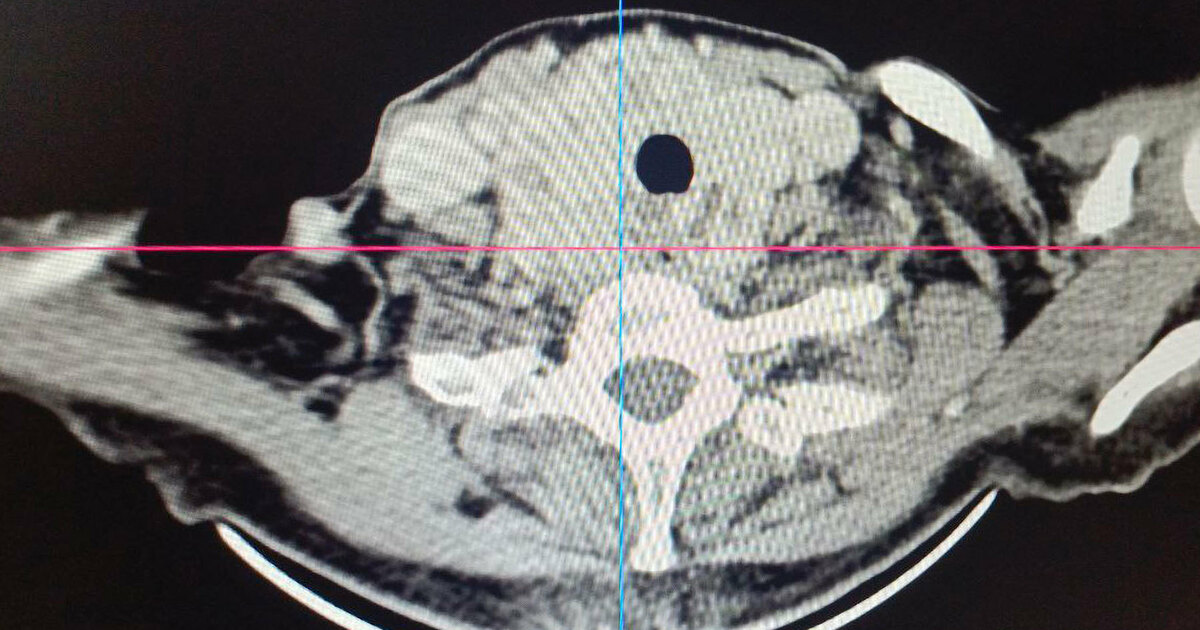

Особую сложность представляло анатомическое расположение зоба. Образование было частично загрудинным и опускалось за грудину примерно на две трети. Правая доля щитовидной железы подходила вплотную к плечеголовному стволу. Зоб циркулярно охватывал трахею, сдавливая ее со всех сторон и вызывая у женщины затруднение дыхания даже при небольшой физической нагрузке.

Из-за такого расположения железы врачи рассматривали возможность рассечения грудины для безопасного доступа, что значительно усложнило бы операцию и восстановительный период.